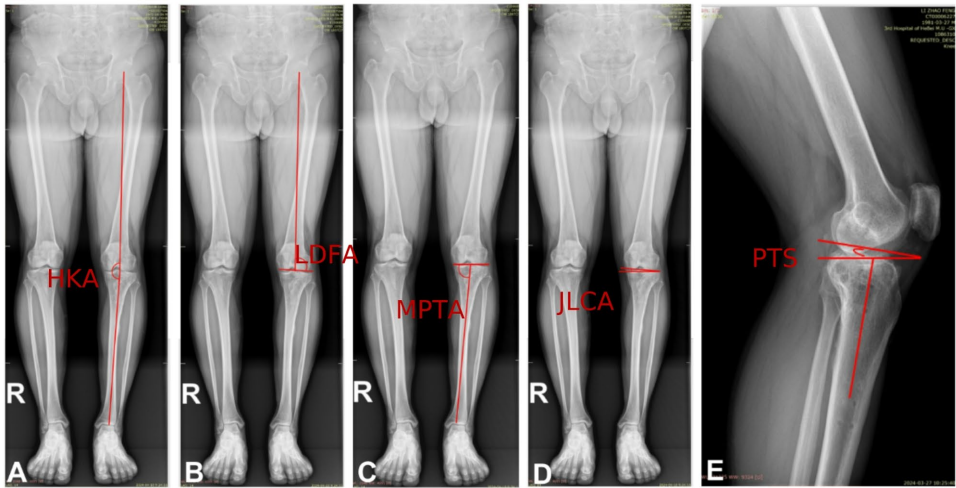

本研究针对胫骨平台骨折(TPFs)术后创伤性骨关节炎(PTOA)风险与骨密度(BMD)关联不明的临床问题,通过分析103例接受双反牵引复位微创术(MIPPO-DRTR)患者的CT骨密度(Hounsfield Units, HU)、膝关节对线参数(HKA/MPTA/LDFA/JLCA/PTS)及功能评分(SF-36/HSS),首次揭示股骨远端与胫骨近端BMD升高与膝关节功能下降、生活质量恶化及内翻畸形加重显著相关(如股骨内侧BMD与HKA负相关,r=-0.320, P=0.017),尤其对高BMI患者影响更显著。该发现为术后骨密度管理优化关节对线、延缓PTOA进展提供了新依据。

河北医科大学第三医院创伤急救中心的研究团队在《Journal of Orthopaedic Surgery and Research》发表的最新研究中,首次通过CT衍生的Hounsfield单位(HU)量化膝周骨密度,揭示了骨矿物质分布与关节畸形演化的深层联系。该研究纳入2015-2018年间103例接受MIPPO-DRTR手术的TPFs患者,平均随访7.37年,采用三大关键技术:

3. 关节对线的骨密度驱动机制